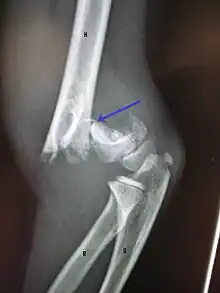

On lateral view of the elbow, there are five radiological features should be looked for: tear drop sign, anterior humeral line, coronoid line, fish-tail sign, and fat pad sign/sail sign (anterior and posterior).[3][8]

Tear drop sign - Tear drop sign is seen on a normal radiograph, but is disturbed in supracondylar fracture.[8]

Anterior humeral line - It is a line drawn down along the front of the humerus on the lateral view and it should pass through the middle third of the capitulum of the humerus.[9] If it passes through the anterior third of the capitulum, it indicates the posterior displacement of distal fragment.[8]

Coronoid line - A line drawn along the anterior border of the coronoid process of the ulna should touch the anterior part of the lateral condyle of the humerus. If lateral condyle appears posterior to this line, it indicates the posterior displacement of lateral condyle.[8]

Fish-tail sign - The distal fragment is rotated away from the proximal fragment, thus the sharp ends of the proximal fragment looks like a shape of a fish-tail.[8]